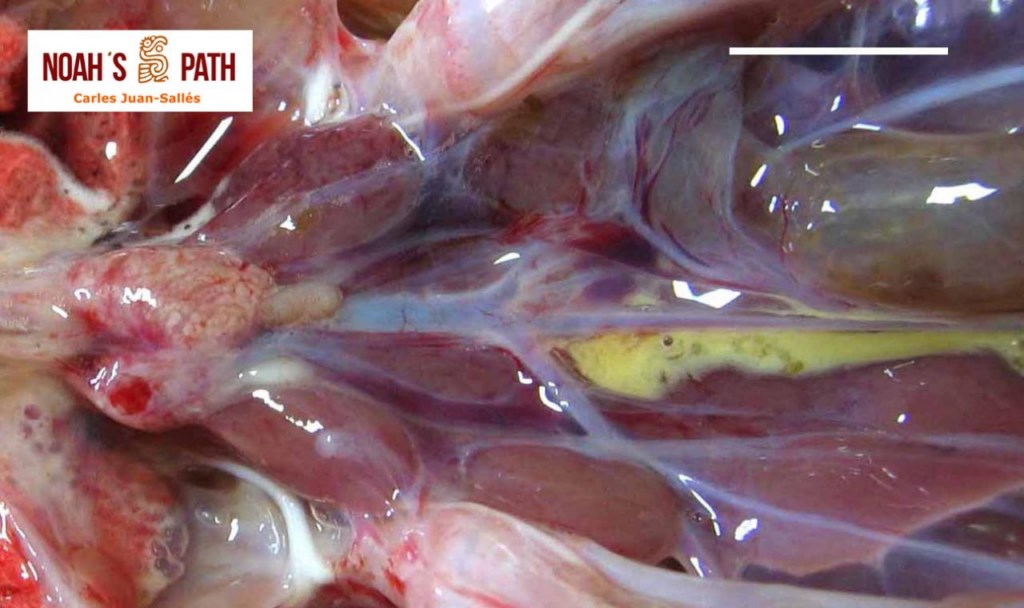

El examen post mortem ofrece una oportunidad única de acceso a todos los tejidos del paciente para diagnóstico de las causas de enfermedad y muerte, y por lo tanto es esencial para medicina preventiva y curativa en grupos de animales, seguimiento de casos, estudios sobre enfermedades, control de zoonosis, medicina de la conservación, y patología forense. En Noah's Path pensamos que un examen post mortem de este tipo de fauna debería ser realizado siempre que sea posible por patólogas/os especializadas/os con el fin de obtener el máximo de información y obtener las muestras más adecuadas.